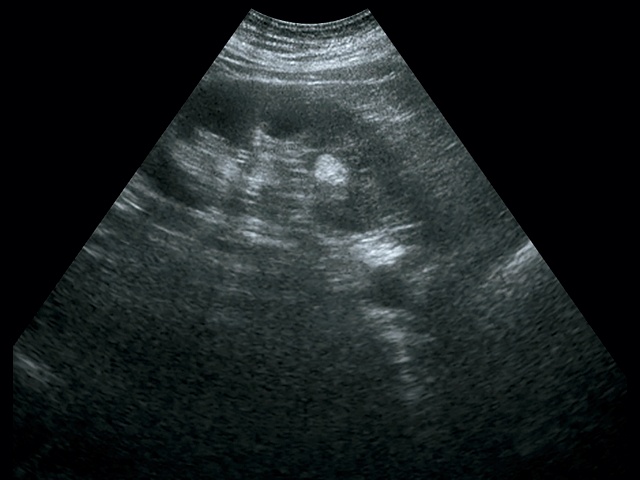

При классической картине АМЛ в почке определяется гиперэхогенное (по отношению к паренхиме почки) образование с четкими контурами, не дающее акустической тени, округлой формы, акустическая плотность которого соответствует плотности жировой ткани, структура опухоли однородная во всех отделах (рис. 2, 3).

В паренхиме почки визуализируется гиперэхогенное образование с четкими контурами, небольшого размера, без акустической тени.